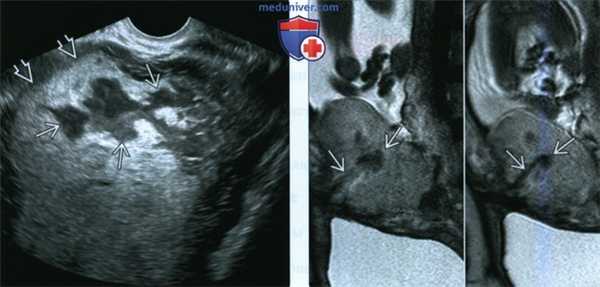

(Слева) Беременность, осложненная ЗРП во II триместре и маловодием. В плаценте определяются несколько эхонегативных образований некоторых из них определяется кровоток.

(Справа) Другой случай. МРТ„ Т2-ВИ. Маловодие и ЗРП. В толще плаценты отмечаются многочисленные гиперинтенсивные очаги При гистологическом исследовании плаценты установлен тромбоз 70% сосудистого русла плаценты, связанный с коагулопатией у матери. Плод погиб внутриутробно.